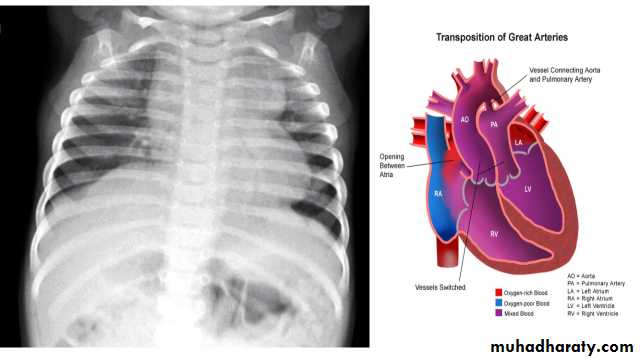

Transposition of the great arteries (TGA) is the most common cyanotic congenital cardiac anomaly with cyanosis in first 24 hours of life. It accounts for up to 7% of all congenital cardiac anomalies

Chest radiograph

A frontal chest radiograph classically shows cardiomegaly with a cardiac contours classically described as appearing like an egg on a string . There is often an apparent narrowing of the superior mediastinum as result of the aortic and pulmonary arterial configuration .

Egg-on-a-string sign ( TGA )